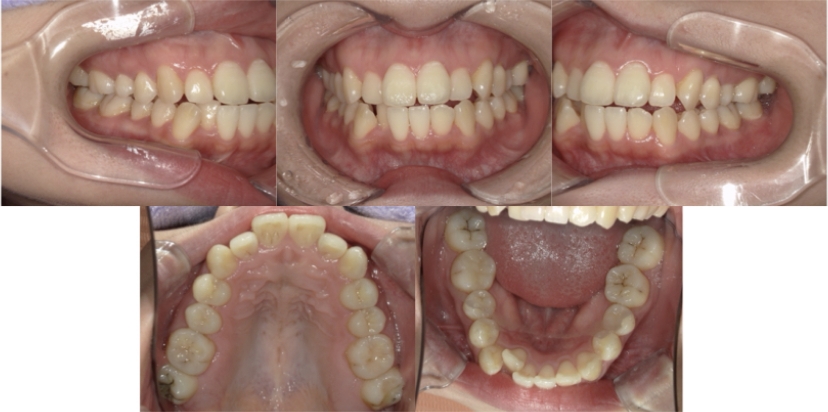

症例4

下顎前突、叢生

抜歯

ブラケット矯正

上下顎叢生、反対咬合(上下の前歯のガタガタ、若干受け口)のケースです。

装置はラビアル(上下表側)で、上下顎の小臼歯を4本抜歯を行っています。抜歯したスペースを使って、上下の叢生改善と前歯の受け口の改善を行っています。

主訴 前歯のガタガタを治したい。

年齢・性別 45歳 女性

お住まいの地域 神奈川県川崎市

治療方針 抜歯スペースを利用して上前歯の叢生(ガタガタ)の改善と受け口の改善

抜歯部位 上顎左右第一小臼歯、下顎左右第二小臼歯

使用装置 ラビアル(上下表側)、顎間ゴム

治療期間 2年6か月

治療回数 20回

リテーナー クリアリテーナー

BEFORE

AFTER